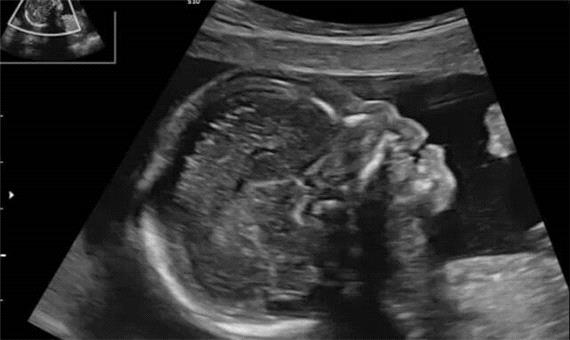

سیاست و بازاریابی - ایسنا /در سال‌های اخیر پیشرفت‌های تصویربرداری در بارداری به پزشکان امکان داده تا زودتر از گذشته ناهنجاری‌های جنینی را تشخیص دهند. یکی از شاخص‌هایی که در این مسیر اهمیت زیادی یافته، وضعیت استخوان بینی جنین است که می‌تواند نشانه‌ای از برخی اختلالات ژنتیکی باشد.

اختلالات کروموزومی مانند سندرم داون از شایع‌ترین ناهنجاری‌های ژنتیکی در میان نوزادان هستند. این وضعیت در حدود یک مورد از هر 800 تولد زنده دیده می‌شود و به دلیل تأثیر آن بر رشد ذهنی و جسمی کودک، شناسایی زودهنگام اهمیت زیادی دارد. از سال‌ها پیش، پزشکان متوجه شدند که نبود یا کوچکی استخوان بینی جنین می‌تواند یکی از نشانه‌های احتمالی سندرم داون باشد. با این حال، این یافته در جمعیت‌های مختلف، از نظر نژادی و جغرافیایی تفاوت‌هایی دارد و همین مسئله ضرورت انجام مطالعات اختصاصی برای هر منطقه را نشان می‌دهد.

در راستای مطالعه بیشتر این موضوع، میترا افتخار یزدی، دانشیار گروه زنان و مامایی دانشکده پزشکی دانشگاه علوم پزشکی سبزوار، به همراه پنج همکار خود، پژوهشی را برای بررسی ارتباط اندازه استخوان بینی جنین با بروز سندرم داون انجام داده‌اند. این مطالعه با هدف یافتن رابطه میان مشاهده یا عدم مشاهده استخوان بینی در دو مرحله از بارداری یعنی سه‌ماهه اول و دوم طراحی شده است تا مشخص شود آیا این شاخص می‌تواند به‌تنهایی معیار مناسبی برای تشخیص زودهنگام ناهنجاری‌های ژنتیکی باشد یا خیر.

در این پژوهش، 265 خانم باردار مراجعه‌کننده به کلینیک پریناتولوژی دانشگاه علوم پزشکی سبزوار مورد بررسی قرار گرفتند. در این مطالعه، جنین‌هایی که در سونوگرافی سه‌ماهه اول استخوان بینی آن‌ها مشاهده نمی‌شد یا در سه‌ماهه دوم دچار کوتاهی غیرطبیعی این استخوان بودند، وارد تحقیق شدند. داده‌های استخراج‌شده از پرونده بیماران با استفاده از نرم‌افزار آماری مخصوص تحلیل شد تا ارتباط میان اندازه استخوان بینی و نتایج ژنتیکی مشخص شود.

نتایج نشان دادند که در سونوگرافی سه‌ماهه اول، حدود 31 درصد از جنین‌ها فاقد استخوان بینی بودند. از میان این موارد، 19 درصد مبتلا به سندرم داون و سایر اختلالات ژنتیکی بودند، در حالی‌که در سه‌ماهه دوم، هرچند درصد بیشتری از جنین‌ها دچار کوتاهی استخوان بینی بودند، اما این ویژگی به‌تنهایی ارتباط آماری خاصی با ناهنجاری‌های ژنتیکی نشان نداد. به بیان ساده‌تر، اگر در ماه‌های اول بارداری استخوان بینی دیده نشود، احتمال وجود اختلال ژنتیکی بالا است، ولی در ماه‌های بعد، کوتاهی آن الزاماً به معنای وجود چنین اختلالی نیست.

محققان نتیجه گرفتند که نبود استخوان بینی در سونوگرافی سه‌ماهه اول می‌تواند به‌عنوان یک شاخص مهم در غربالگری‌های پیش از تولد مورد توجه قرار گیرد، اما در سه‌ماهه دوم نمی‌توان تنها بر پایه اندازه کوچک استخوان بینی تصمیم‌گیری کرد. به عبارت دیگر، در نیمه دوم بارداری لازم است عوامل دیگری مانند سایر شاخص‌های سونوگرافی یا سوابق خانوادگی نیز بررسی شود تا تشخیص دقیق‌تر صورت گیرد.